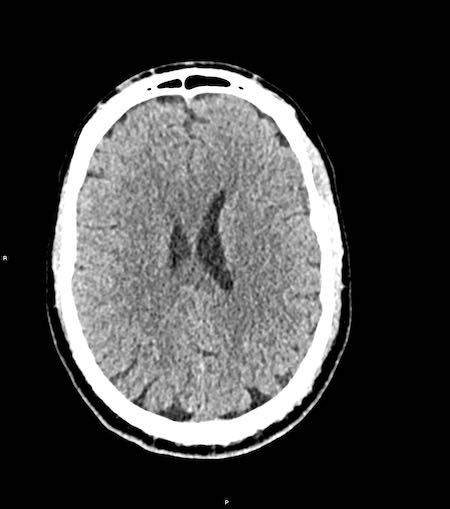

Bệnh nhân này có tụ máu dưới màng cứng cấp tính.

Có sự dịch chuyển đường giữa (hình bên trái).

Bệnh nhân đã được phẫu thuật và khối tụ máu được dẫn lưu (hình bên phải).